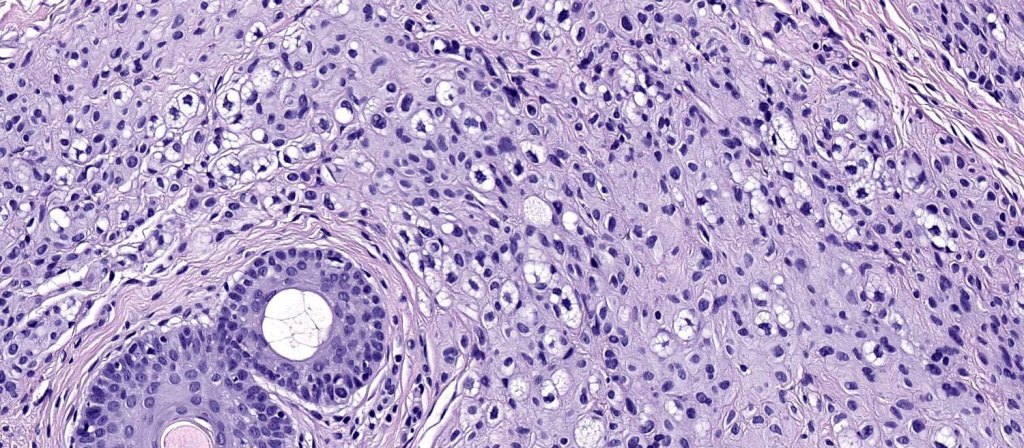

Histological features

.Balloon cell change is most often seen in banal melanocytic nevi but it has also rarely been described in cellular blue nevus, dysplastic nevus, combined nevus, halo nevus & Spitz nevus. Lesions with <50% of balloon cells are sometimes described as nevi with balloon cells. Nevi with >50% balloon cells are described as balloon cell nevus.

.Balloon cell nevs genrally has uniform, hyperchromatic nuceli (as opposed to the vesicular nuclei with prominent nucleoli) seen in melanoma. Mitoses are absent.(In my experience, balloon cell melanoma is more common than balloon cell nevus).

. In some balloon cell nevi, the microvesicles may result in nuclear scalloping reminiscent of a sebaceous tumor. In cases where there is real doubt, immunohistochemistry (S100), SOX10) will resolve the problem.

The importance of the entity is that it must always be distinguished from balloon cell melanoma. All cases should be scrutinized very carefully for pleomorphism and mitotic activiy before rendering a diagnosis of balloon cell nevus.